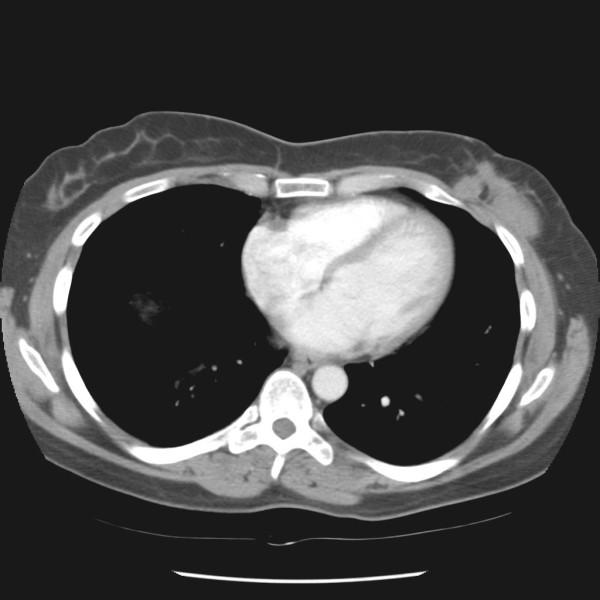

CASE PRESENTATION

We report a patient with three post-surgical recurrences of fibromatosis of the breast over a seven year period. The fibromatosis was found to be involving the chest wall musculature and causing persistent and worsening pain. An aggressive operative strategy was undertaken, consisting of mastectomy with en bloc resection of the underlying chest wall musculature, ribs, and parietal pleura.

病例报告

我们报告一名患者,在七年时间里乳腺纤维瘤病术后复发三次。发现纤维瘤病累及胸壁肌肉组织并导致持续且加重的疼痛。采取了积极的手术策略,包括乳房切除术并整块切除下方的胸壁肌肉组织、肋骨和壁层胸膜。